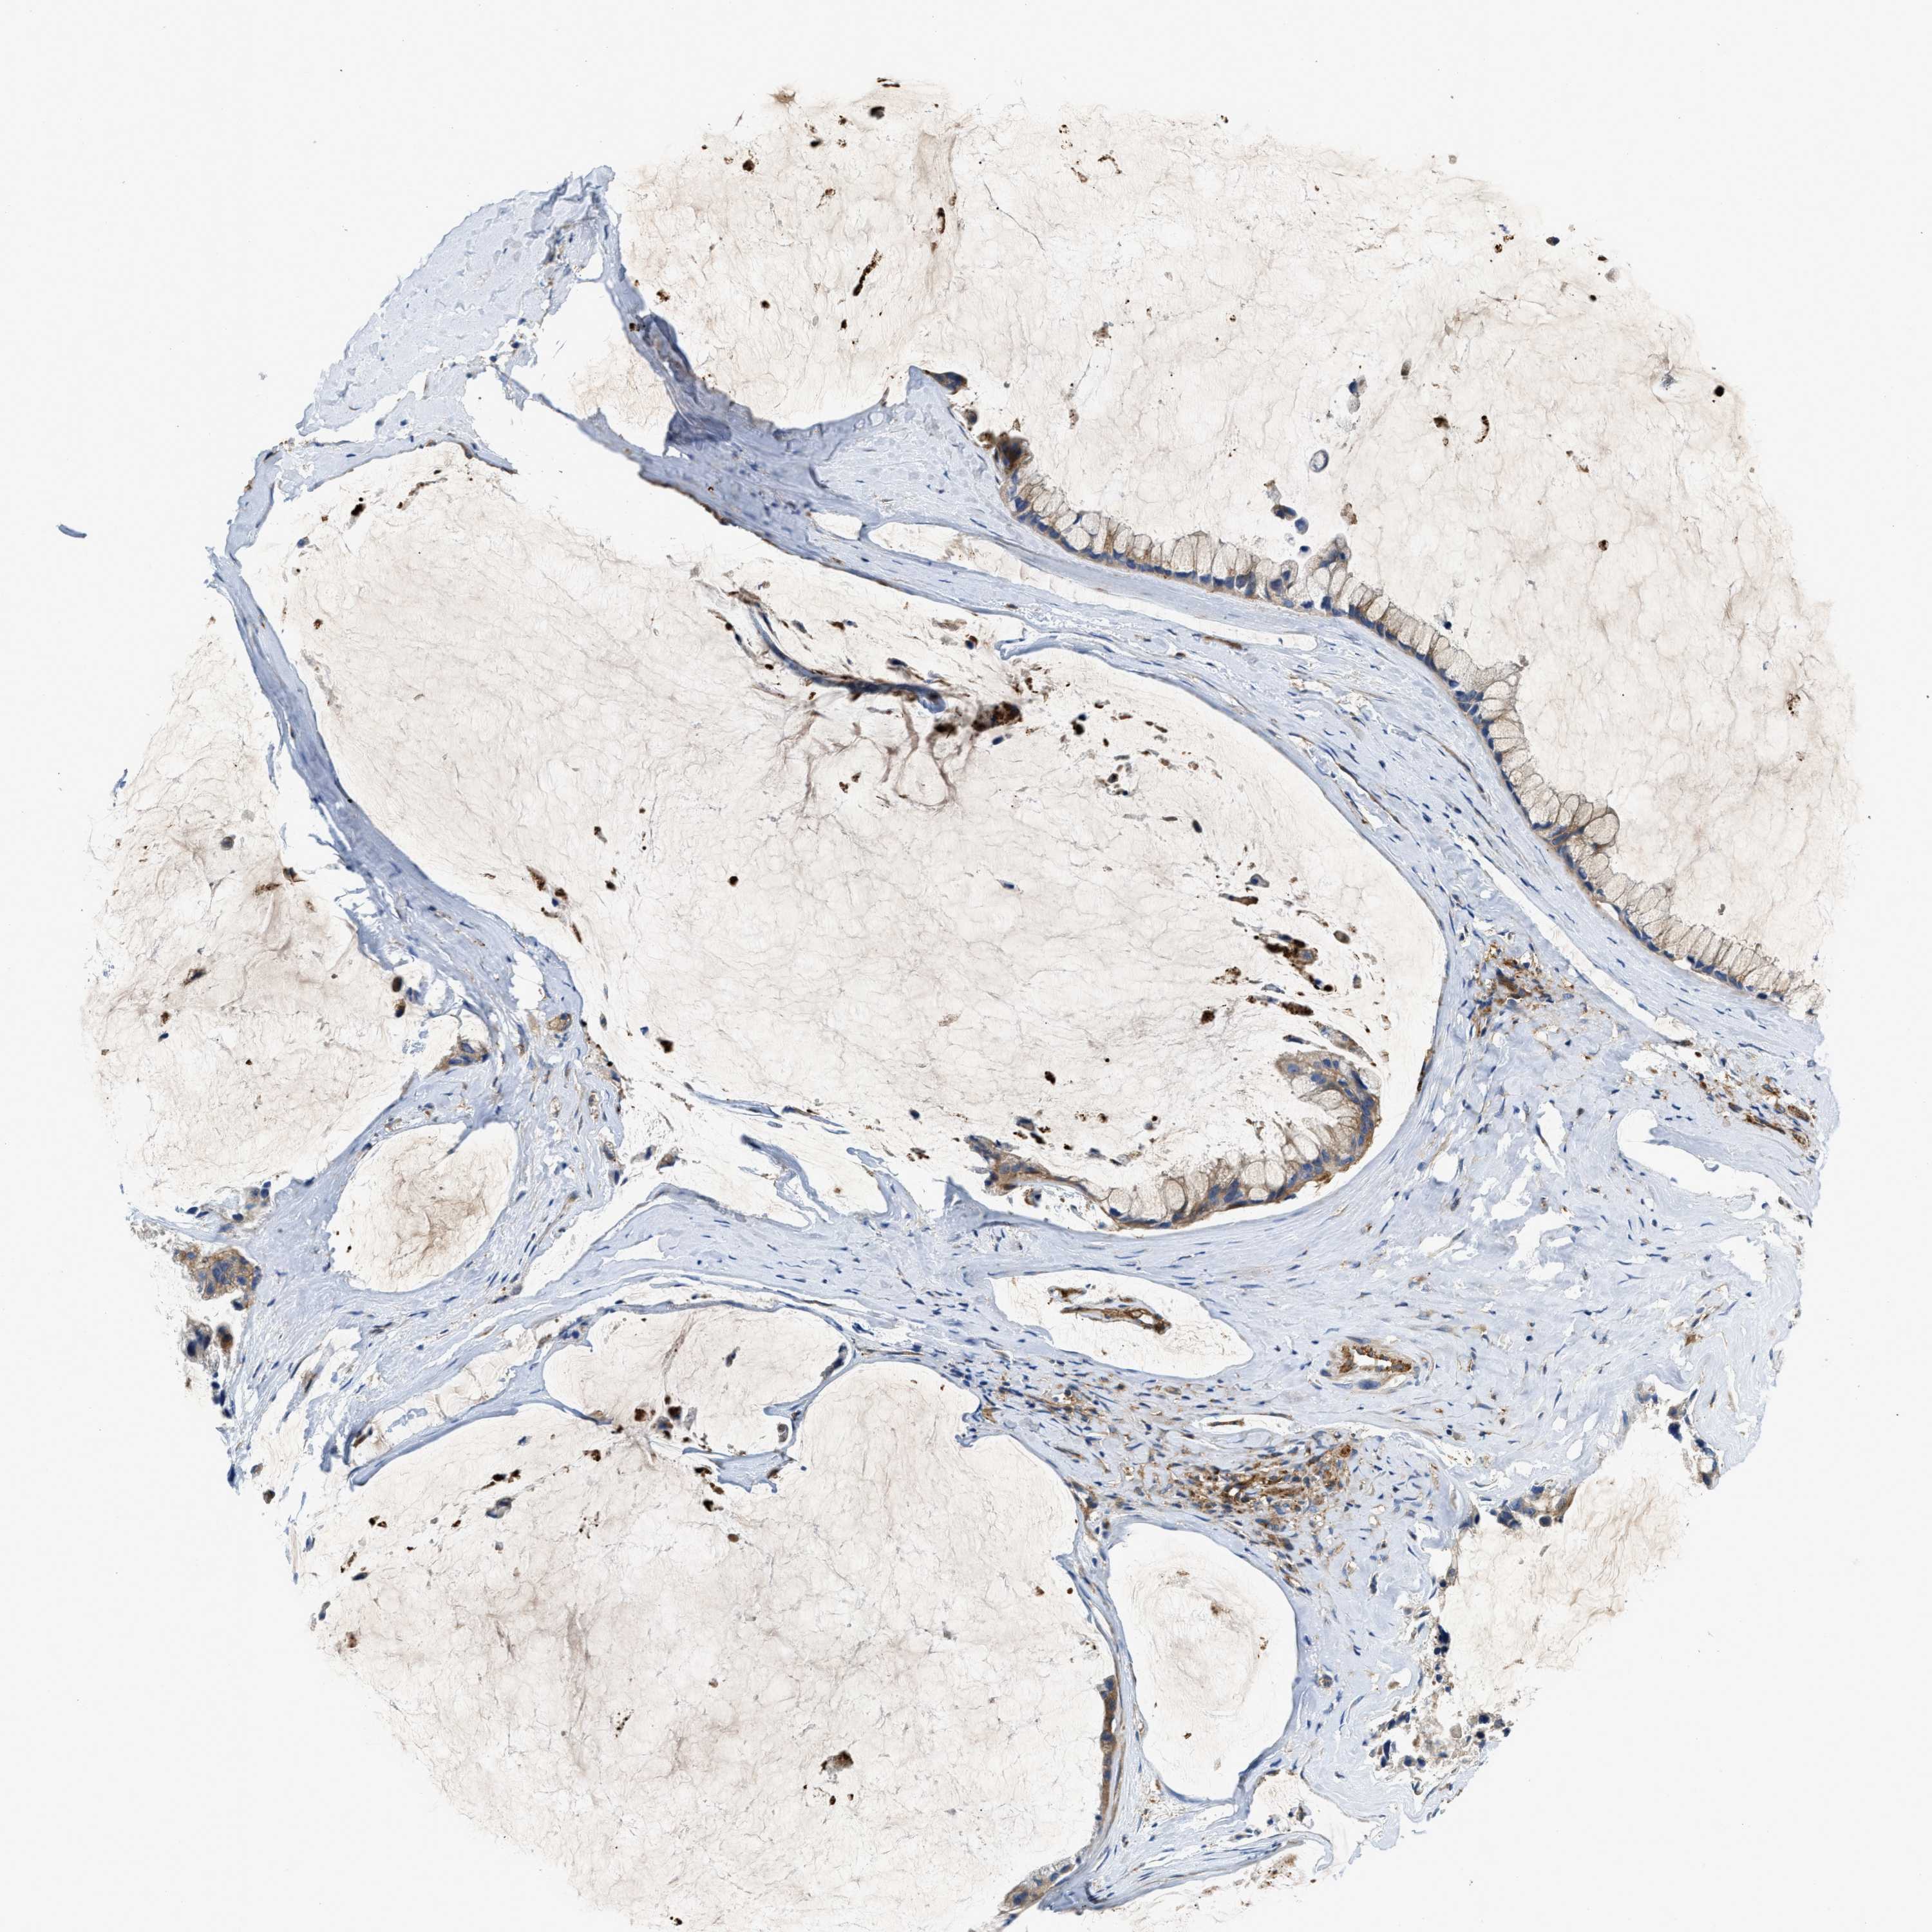

OVARIAN CANCER - Protein expressioni

A mouse-over function shows sample information and annotation data. Click on an image to view it in a full screen mode. Samples can be filtered based on level of antibody staining by selecting one or several of the following categories: high, medium, low and not detected. The assay and annotation is described here.

Note that samples used for immunohistochemistry by the Human Protein Atlas do not correspond to samples in the TCGA dataset.

Antibody stainingi

Antibody staining in the annotated cell types in the current human tissue is reported as not detected, low, medium, or high, based on conventional immunohistochemistry profiling in selected tissues. This score is based on the combination of the staining intensity and fraction of stained cells.

Each image is clickable and will lead to virtual microscopy that enables deeper exploration of all samples and also displays staining intensity scores, fraction scores and subcellular localization as well as patient and tissue information for each sample.

Antibody HPA020653

Cystadenocarcinoma, serous, NOS

Carcinoma, endometroid

Cystadenocarcinoma, mucinous, NOS

Carcinoma, NOS